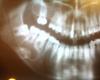

Bier Опубликовано 19 февраля, 2010 Поделиться Опубликовано 19 февраля, 2010 http://cs729.vkontakte.ru/u3941812/93641194/x_81985c3d.jpg Если киста одонтогенная (имеет свое начало от зубов) то терапевтическое лечение возможно. Но не факт, что поможет. Но нужен _очень_ грамотный стоматолог терапевт. Первый попавшийся однозначно не подойдет.Если же киста имеет другие причины, то только операция. Нерв там проходит не лицевой, а тройничный. Он дает чувствительную иннервацию зубам и н. губе с этой стороны. При его травмировании паралича не наступает. Пропадает чувствительность, двигательные функции сохраняются. Что-то делать безусловно нужно. Киста может и нагноиться в любой момент и начать расти, повредить тройничный нерв и быть причиной перелома челюсти. Ссылка на комментарий

Bier Опубликовано 22 февраля, 2010 Поделиться Опубликовано 22 февраля, 2010 судя по задаваемым вопросам так не очень то понимаете.К слову сказать н.ч. канал (в котором нерв) у вас довольно далеко от корней зубов. Ссылка на комментарий